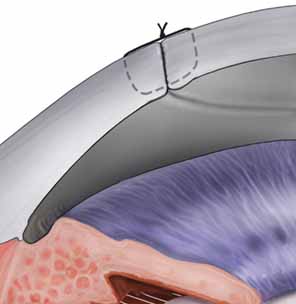

The tissue is tipped by rotating the wrist and the Paton spatula so that the graft is positioned almost perpendicularly to the host cornea. This position facilitates a precise grasping of the top edge of the donor tissue by split-tined Hofmann-Polack forceps (Fig. 5). These speciallydesigned forceps allow for the uninterrupted passage of a needle between the two toothed tines. After the elevated edge of the graft is grasped by the Hofmann-Polack forceps, the surgeon quickly exchanges the Paton spatula for a preloaded needle driver containing a 10-0 nylon suture. The suture is first placed onto the donor cornea at the 12 o'clock position. The action of suture placement involves not only the passage of the needle onto the graft tissue, but also the placement of the graft tissue onto the needle. In this sense, one can think of “placing the graft onto the needle” in addition to passing the needle through the graft. The optimal exit depth of the suture is approximately 90% thickness, with the exit path extending radially through the stromal side cut of the donor graft tissue (Fig. 6). The donor tissue is released by the Hofmann-Polack forceps, and then the host rim is grasped.

Fig. 6 Suturing technique for penetrating keratoplasty. Forceps are used to approximate the edges of the host and donor cornea, while the suture is placed at approximately 90% depth.

The previously placed methylene blue radial keratotomy marks are used to guide the positioning of the 12 o'clock suture pass. The suture is passed though the two tines of the forceps, making sure that the pass is completed in as radial an orientation as possible. The ratio of the distance from the entry of the needle on the donor to the exit on the host cornea is ideally one-third donor to two-thirds host. The Hofmann-Polack forceps are then exchanged for 0.12 mm Maumenee forceps. The suture is tied in place using a slipknot (two-one throw) and then cut using Vannas corneal scissors (Fig. 7). Both tags can be left long so as to be able to adjust suture tension based on intraoperative keratoscopy after the placement of the first eight sutures. The cut sutures are gently draped away from the visual axis, and the donor tissue is grasped at the 6 o'clock position, 180 degrees away from the first suture. A similar technique is used in passing the suture at this position. Symmetry of the pass can be estimated by noting the tissue alignment as well as the symmetry at 3 o'clock and 9 o'clock. Also, as gentle tension is applied in tying the suture, a straight tension line will be noted in the graft tissue. This line should be oriented from 6 o'clock to 12 o'clock. Sutures are then passed at the 3 o'clock and 9 o'clock meridians, while taking into account the amount of tissue on either side of the pass. Upon completion of the four cardinal sutures, a symmetric diamond shape should be noted on the donor tissue. A total of eight interrupted sutures are placed, the ends of which are temporarily left long. The graft is then wetted with balanced salt solution, and a manual keratoscope, such as a circular metal loop or a von Luhnen keratoscope, is used to estimate astigmatism based on the compression or expansion of the reflected rings or ovoid reflex from the corneal surface. If suture adjustment is needed, the suture is grasped proximal to the knot. The suture is cut and rotated by pulling the grasped suture. The tension of the suture can then be adjusted by retying the knot based on keratoscopy. For the slipknots not needing adjustment, a third locking throw is placed. The details of suture adjustment to minimize postoperative astigmatism are discussed more thoroughly in the suturing techniques section.

Fig. 7 Suturing technique for penetrating keratoplasty. Schematic illustration showing the 10-0 nylon suture at proper depth after the suture is tied in a slipknot fashion. The knot will then be rotated and buried in the cornea.